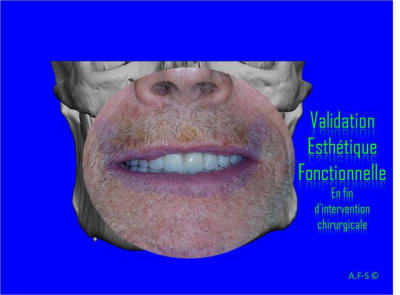

Extraction, pose d’implants Ankylos, pose des piliers Standard définitifs, mise en charge immédiate bi-maxillaire en une chirurgie.

Maxillaire supérieur – extraction 13, 26, 7 implants en MCI, 1 implant en MCR pose summeurs, densification par ostéotme, comblement osseux, bridge provisoire sans fausse gencive avec renfort métallique.

Maxillaire inferieur – extraction 35, 34, 44, 45, 6 implants MCI, comblement osseux, bridge provisoire sans fausse gencive avec renfort métallique.

Le patient présente une perte de DV importante qui doit être corrigé avec les bridges provisoires.